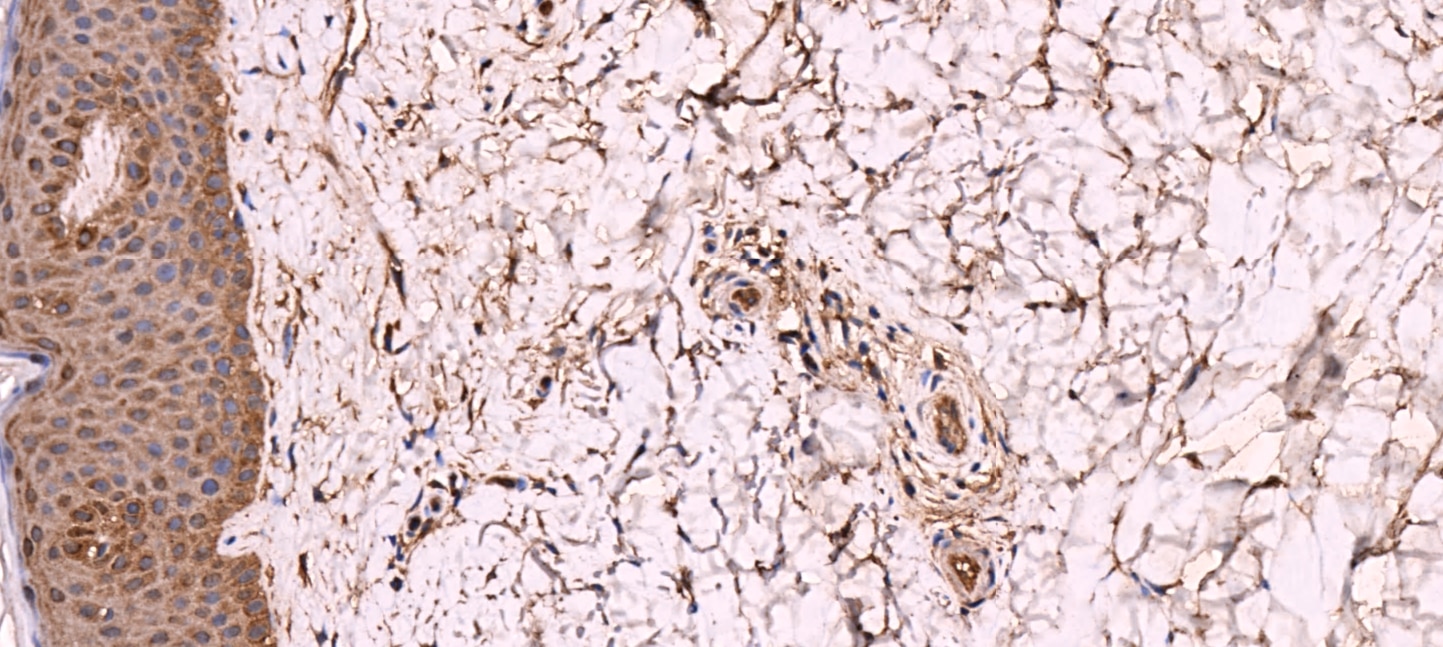

| Images | Ratings | Applications | Species | Date | Details | ||||||||

Enlarge |

reviewed by:

Verified Customer |

IHC-P | Human | 12/08/2016 |

Summary

|